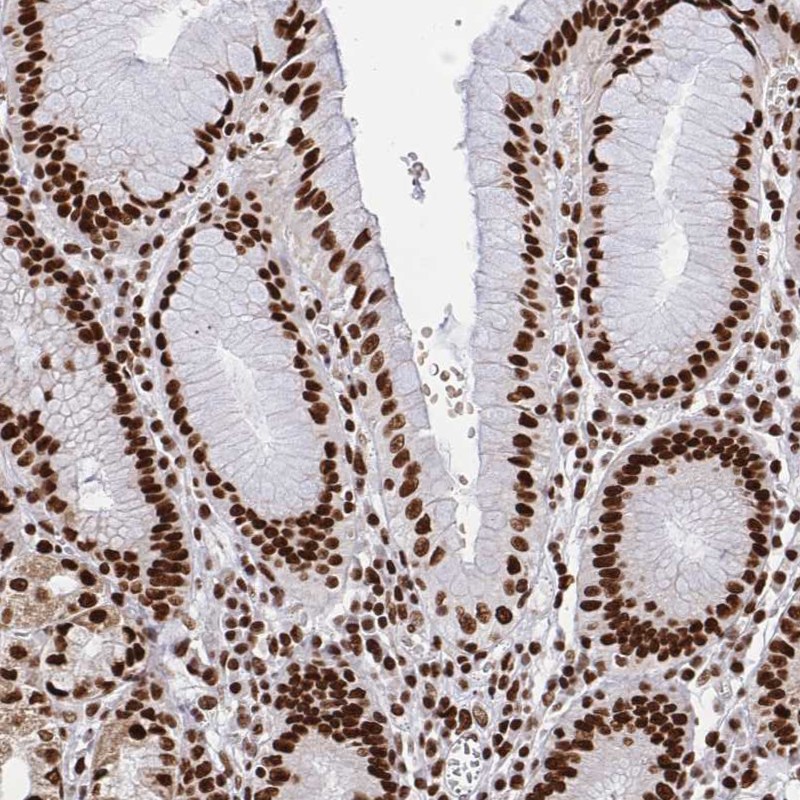

Immunohistochemical staining of human stomach shows strong nuclear positivity in glandular cells.